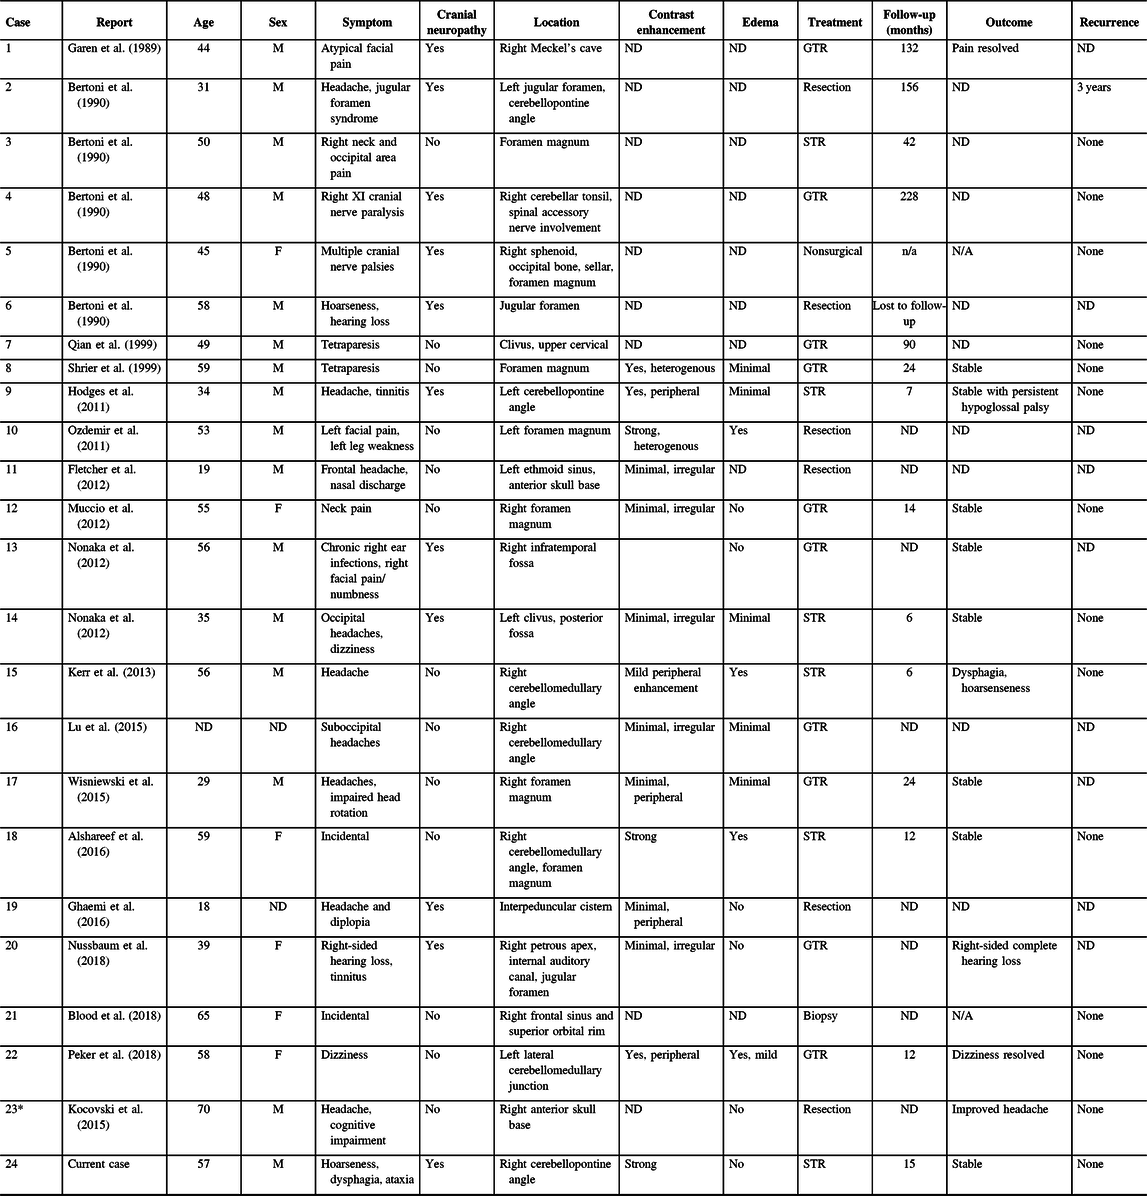

Our literature search identified 113 potentially relevant records. After abstract and full-text screening, 18 records were identified including 23 unique cases of skull base CAPNONs (Figure 5, Table 1).Reference Alshareef, Vargas, Welsh and Kalhorn4,Reference Garen, Powers, King and Perot7–Reference Kocovski, Parasu, Provias and Popovic11,Reference Bertoni, Unni, Dahlin, Beabout and Onofrio13–Reference Wisniewski, Janczar, Tybor, Papierz and Jaskolski24 All 24 patients (including our previously unpublished case) were symptomatic, with 11 (45.8%) patients presenting with cranial neuropathies (Table 1).Reference Garen, Powers, King and Perot7–Reference Nonaka, Aliabadi, Friedman, Odere and Fukushima9,Reference Bertoni, Unni, Dahlin, Beabout and Onofrio13,Reference Hodges, Karikari and Nimjee16,Reference Nussbaum, Hilton and Defillo20 One patient (Case 5) was managed conservatively,Reference Bertoni, Unni, Dahlin, Beabout and Onofrio13 and one patient (Case 22) underwent a biopsy of the lesion,Reference Blood, Rodriguez, Nolan, Ramanathan and Desai14 while the rest underwent resection of the lesion. Analysis of patients with documented extents of resection revealed that 10 patients underwent gross total resection and 6 underwent subtotal resection of CAPNONs. Among all 24 patients, only 2 patients (Cases 1 and 23) had complete resolution of the symptoms postoperatively,Reference Garen, Powers, King and Perot7,Reference Peker, Aydin and Baskaya22 while most patients remained stable.

Table 1: Skull base CAPNONs reported in the literature

CAPNON = calcifying pseudoneoplasm of neuraxis; F = female; GTR = gross total resection; M = male; STR = subtotal resection; ND = not documented.

* Case 23 was previously published in our center and reanalyzed in the present study.

Among 11 patients with cranial neuropathies, the outcomes of cranial neuropathies were documented in 6 patients.Reference Garen, Powers, King and Perot7,Reference Nonaka, Aliabadi, Friedman, Odere and Fukushima9,Reference Hodges, Karikari and Nimjee16,Reference Nussbaum, Hilton and Defillo20 Two patients had a sacrifice of the CN function with surgical approaches (Cases 1 and 21),Reference Garen, Powers, King and Perot7,Reference Nussbaum, Hilton and Defillo20 while the remaining four patients (Cases 9, 13, 14, and 24) remained stable with persistent cranial neuropathies.Reference Nonaka, Aliabadi, Friedman, Odere and Fukushima9,Reference Hodges, Karikari and Nimjee16 Another patient (Case 15) had new CN X palsy postoperatively, which was responsive to medical management.Reference Kerr, Borys, Bobinski and Shahlaie17 Jugular foramen CAPNONs were reported in three other cases, of which two cases were not followed clinically (Cases 6 and 21).Reference Bertoni, Unni, Dahlin, Beabout and Onofrio13,Reference Nussbaum, Hilton and Defillo20 The third patient (Case 2) initially underwent an intralesional excision and had disease progression at 3 years requiring repeat surgical intervention.Reference Bertoni, Unni, Dahlin, Beabout and Onofrio13 Notably, this was the only reported case of CAPNON recurrence in the series of 24 patients.

The etiology of CAPNON remains unclear, but a reactive process is favored for its pathogenesis. Our first case was a right-sided CPA CAPNON which occurred in a patient with right-sided mastoid effusion. Our second case was a right basal frontal CAPNON in a patient who had remote encephalitis caused by West Nile Virus, with the CAPNON adjacent to the areas of encephalomalacia caused by the previous neurological insult. Both of these cases of CAPNONs occurred in the close vicinity to a separate, and possibly preceding infectious/inflammatory process, further supporting the notion that CAPNON is a reactive proliferative process associated with inflammation and/or injury.Reference Aiken, Akgun, Tihan, Barbaro and Glastonbury3 In reviewing other published cases of skull base CAPNONs, we found that past medical history was not available in the majority. However, Nonaka et al. published a case of a right-sided infratemporal CAPNON in which their patient presented with chronic right-sided ear infections (Table 1).Reference Nonaka, Aliabadi, Friedman, Odere and Fukushima9 While it cannot be concluded that the ear infections preceded the CAPNON, its close vicinity suggests they may be related.